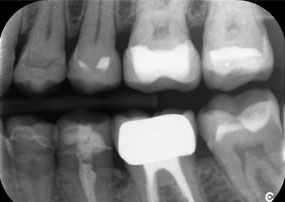

Предизвикателството беше да се премахнат дванадесет блок корони, изработени от сплав от неблагородни метали, без да се повредят подлежащите опорни зъби. Наконечникът беше използван за прецизно разрязване на керамичните слоеве и разделяне на металната конструкция с помощта на карбиден борер, което позволи минимално травматично отстраняване на короните. Само за 30 минути старите възстановявания бяха отстранени, което позволи подготовката на нова протеза, състояща се от циркониеви корони с пълна анатомична форма в задната част и фасети във фронталната зона. Резултатът беше цялостна реставрация, която осигури както функционален, така и естетичен успех (виж фиг. 1).

Вторият случай, който подчертава клиничните възможности на Power Edition е свързан с подмяната на увредена циркониева корона при 63-годишна пациентка. Пациентката беше с отчупена фасета на 20-годишната си циркониева корона на зъб 6. Въпреки че дефектът беше в задната област, пациентката намираше дефекта за притеснителен и поиска нова реставрация.

Power Edition позволи прецизно разрязване, като увеличеният въртящ момент и подобреното охлаждане допринесоха за контролираното отстраняване на короната без значителна загуба на материал. Системата на цангата и повишеният въртящ момент се оказаха от съществено значение в този процес.